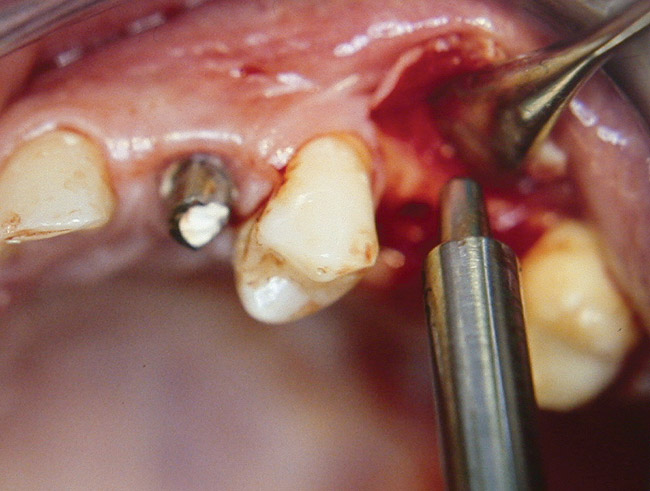

Case 3

A 53-year-old female was referred for evaluation of a fracture of tooth No. 24. The tooth had been treated endodontically 5 years prior. The radiograph revealed a complete fracture of the tooth involving the crown (Figure 12). Tooth extraction and immediate placement of a an implant that was 10 mm in length and 3.75 in diameter was planned.

At the time of surgery, the tooth was extracted without harvesting any mucosal flap because the implant site was prepared by means of a pilot drill bur (Figure 13) and alternating osteotomes (Figure 14A and Figure 14B). The implant was positioned and showed primary stability. The implant was loaded 2 days after surgery. Then, splinted PFM crowns supported by custom gold abutments were delivered. At 6 months posttreatment, the radiograph revealed no bone resorption and the clinical result was optimal (Figure 15A and Figure 15B).

Figure 14A and Figure 14B Alternating osteotomes were used to prepare the implant site.

Figure 14a  Alternating osteotomes were used to prepare the implant site.

Figure 14a

Figure 14b  Alternating osteotomes were used to prepare the implant site.

Figure 14b